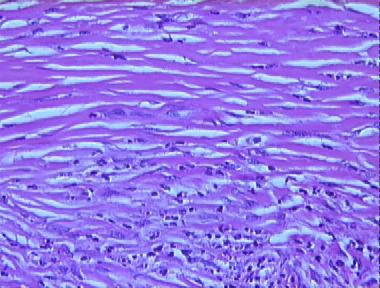

erythema elevatum diutinum, late nodular stage

Histologic Features